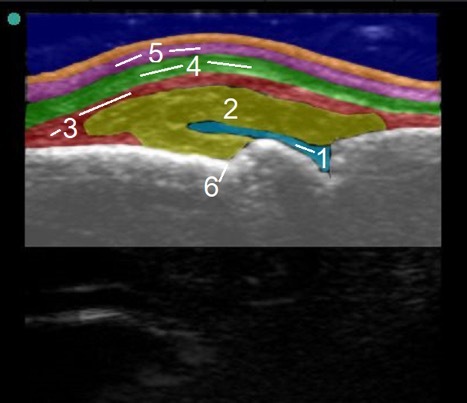

Hand MCP Joint Dorsal Normal vs Inflammatory Synovitis Image

1. Synovial Fluid

2. Joint Capsule

3. Aponeurosis

4. Extensor Tendon

5. Extensor Hood

6. Metacarpal Notch